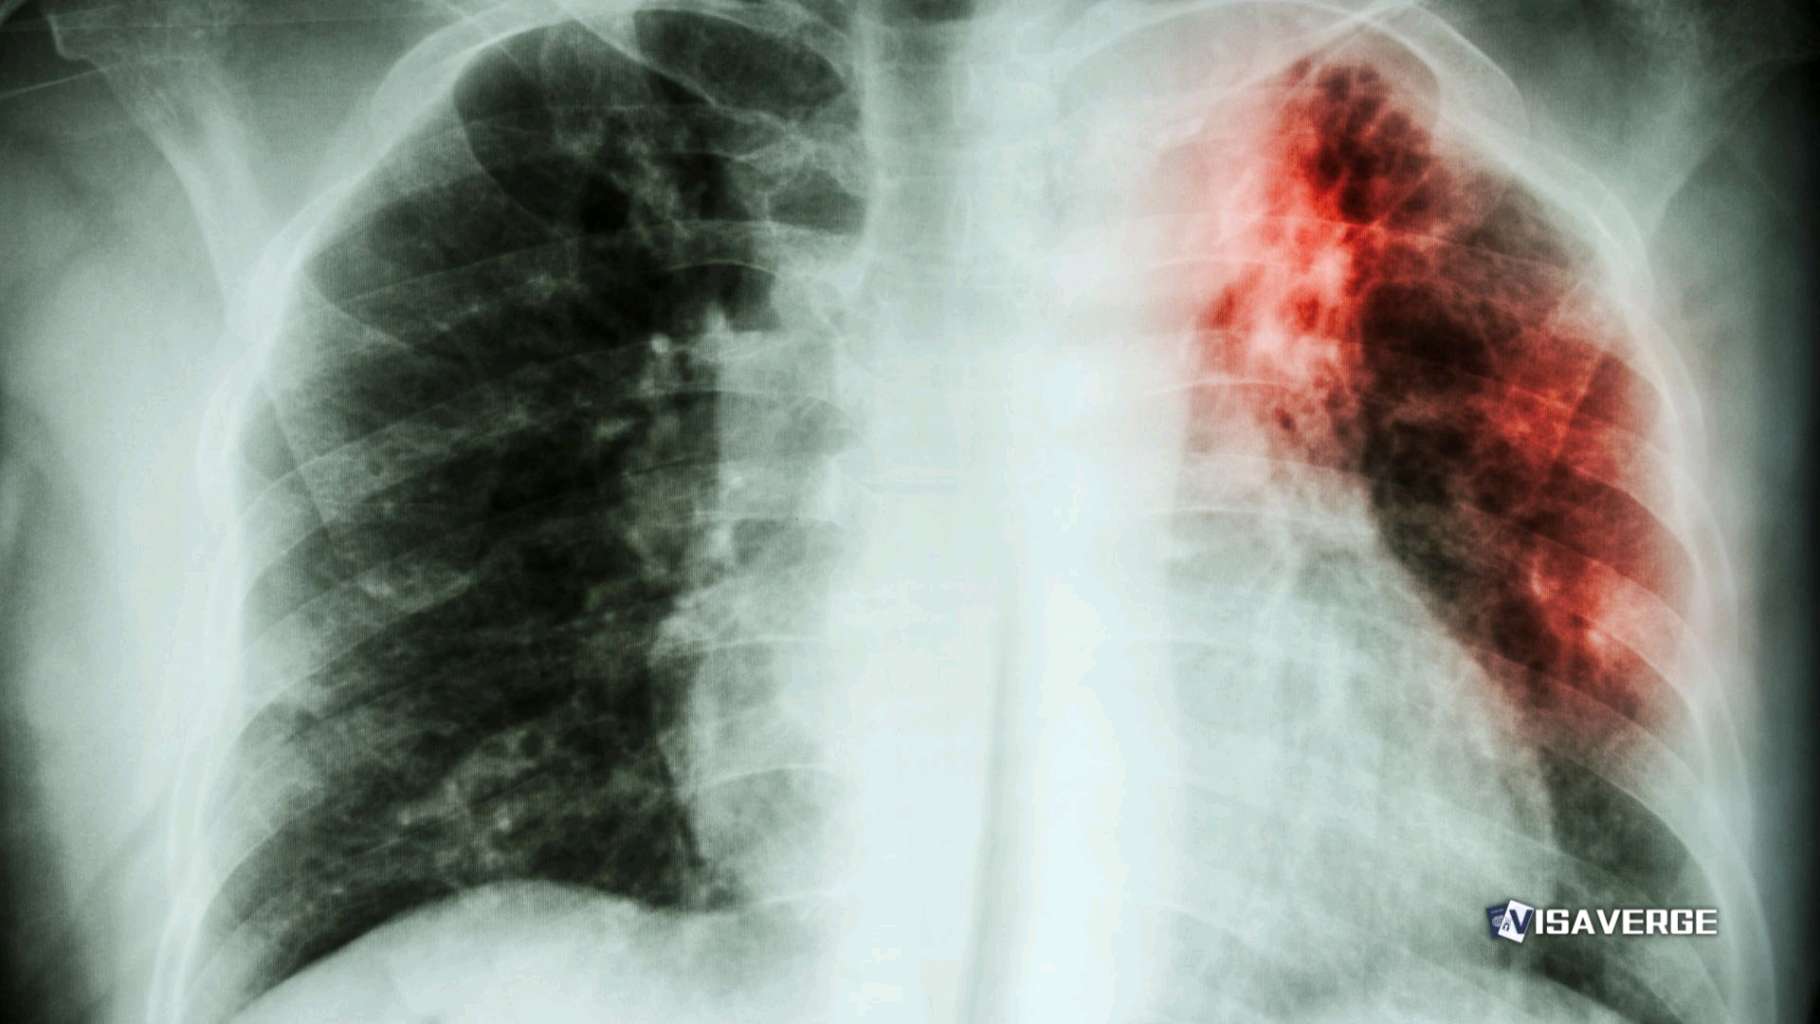

The type of tuberculosis involved here is alarming due to its resistance to medications. Usually, TB impacts the lungs but can attack other body parts as well. Standard medicines can’t easily treat this resistant strain, raising the chances of not only severe illness but also easier spreading to others.

According to Louisiana’s Surgeon General Ralph Abraham, such strains typically are from distant places, emphasizing the need for strong health checks for new arrivals in detention. While the primary patient now shows no symptoms and is under proper medical care, continual attention is crucial to stall further spread.